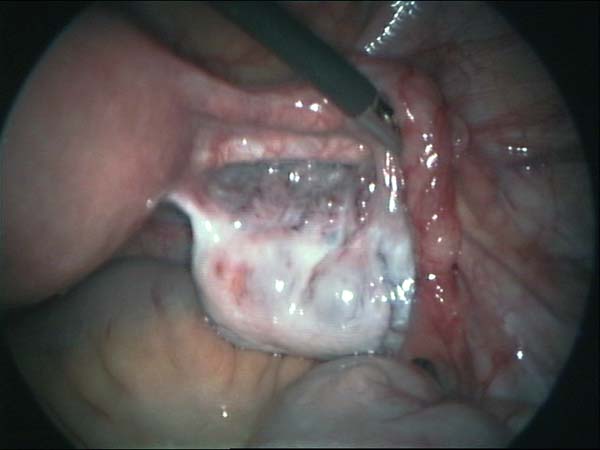

Laparoscopy Photos of ovaries and Fallopian tubes Hydrosalpinx | Dr N Layyous

Laparoscopy Photos of ovaries and Fallopian tubes Hydrosalpinx